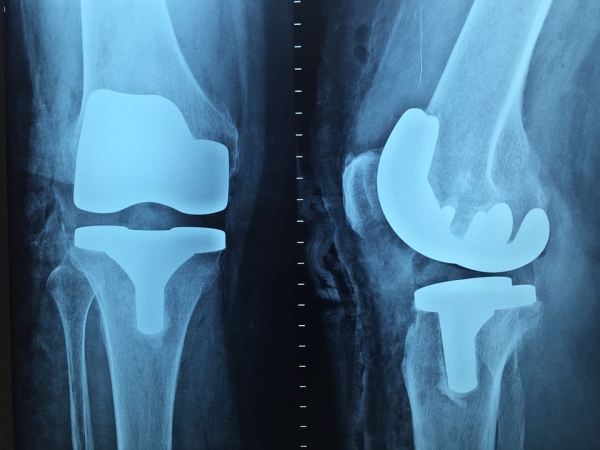

4. 수술 방식별 무릎 인공관절수술비용 차이

무릎 인공관절 수술에는 여러 방식이 있습니다. 각 방식에 따라 비용이 달라질 수 있으니 비교해보세요.

- 전통적 방식

일반적으로 가장 저렴한 방식입니다. 하지만 수술 후 회복 시간이 길어질 수 있습니다. - 로봇 보조 수술

정밀도가 높은 로봇 보조 수술은 비용이 더 높지만, 회복 속도가 빠르고 결과가 안정적입니다. 평균 비용은 약 1,200만 원 이상입니다. - 부분 인공관절 수술

무릎 전체가 아닌 일부만 교체하는 방식으로, 비용은 평균 700만 원에서 900만 원입니다.